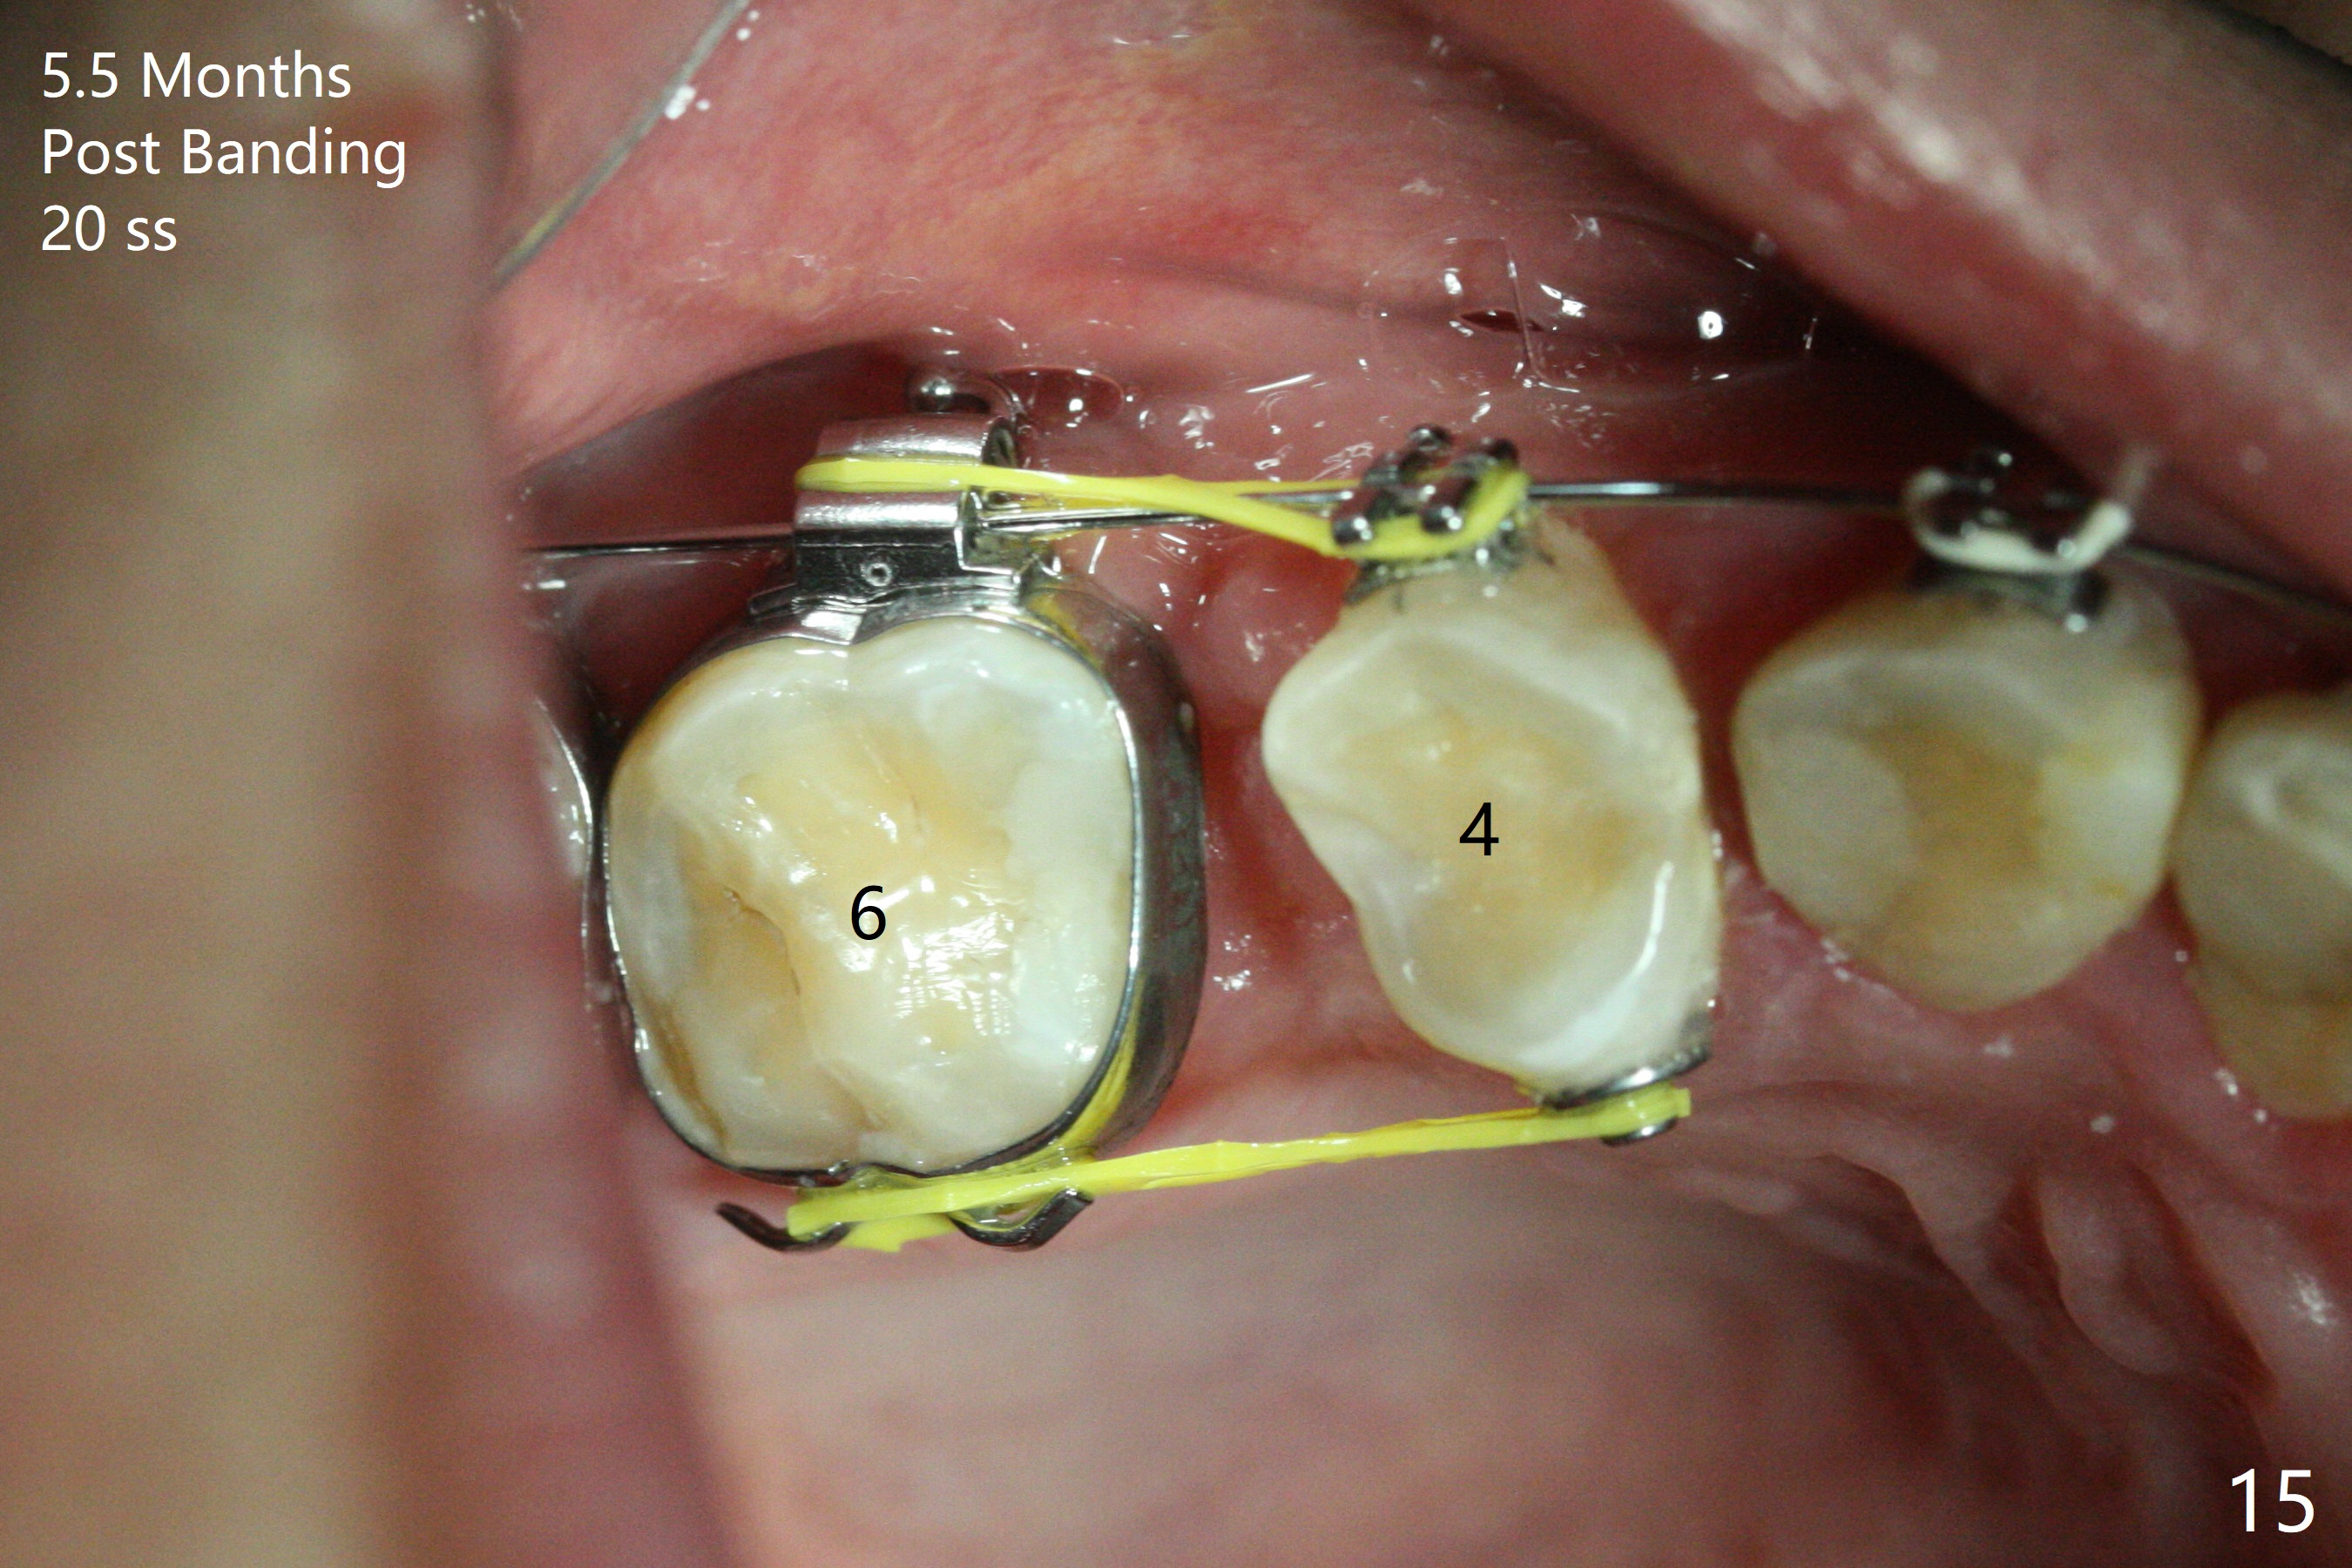

Severe crowding (Fig.1-7) appears to be alleviated especially 2 months after UR5 extraction. Diastemata seem to form mesial and distal to UR2 (Fig.8). Because of severe wear at UR3 (Fig.6), there is no bracket placement differential around it (Fig.8 (14 niti wire)). Lower bands and brackets are placed a week later (Fig.9-11). Because of tight space between LR4 and the opposing tooth (Fig.10), band adhesive is applied to L7 occlusal surface to open the bite (Fig.9). There is an abrupt kink of 12 niti wire between LL4 and 6 (Fig.11). The latter does not improve much in a month; the wires remain the same (Fig.12). For LL2, LR4 has been retracted for ~ 1 month (Fig.13). There is mild tension when 18 ss wire is inserted between LL4 and 6 five point five months post banding (Fig.14). UR4 has been distalized for a month using buccal power chains x3 resulting in rotation; to counter the rotation, a lingual button is placed with power chain x3 lingual and x2 buccal (Fig.15). With space gaining, it is time to finish definitive filling (Fig.16 *). Next visit check midlines, overjet, interdigitation, and molar classification. R4s distalize, but associate with rotation because of power chains buccal and lingual 8 months post banding (Fig.17,18). With the use of the same wires, power chains are applied lingual to continue distalization and rotation correction (Fig.20,21). Lingual buttons are placed at L2s buccalization (Fig.19) and mesialization (Fig.22,23). It appears that space should be created distal to LR3. That is that the lower anterior teeth should be shifted to the right, although it may be not appropriate for the midline.